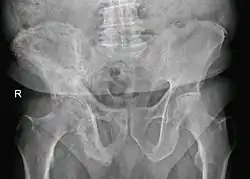

Paget's disease of right pelvic bone. Man of 80 years age.